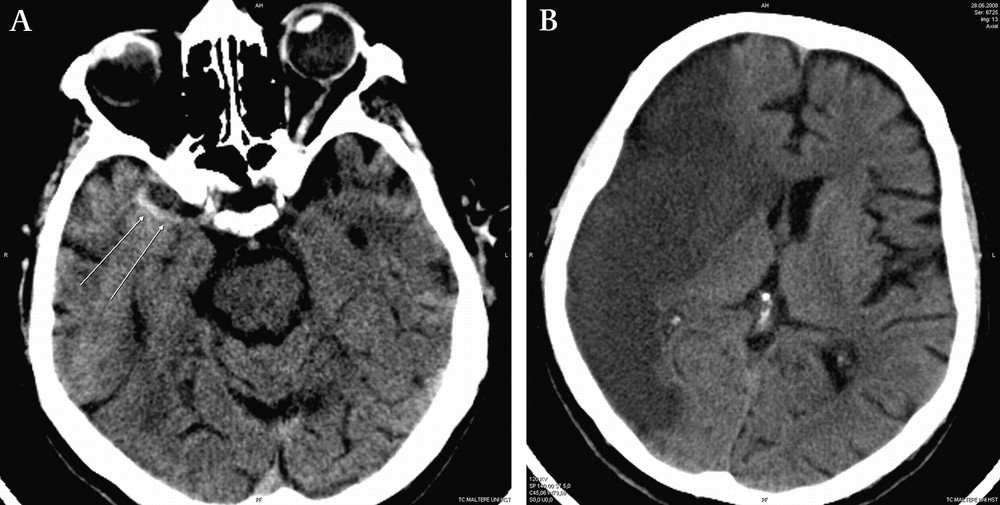

뇌경색은 뇌 혈관이 막혀서 일어나는 상황을 의미합니다. 이로 인해 뇌 조직이 손상을 입을 수 있습니다. "경색"이라는 용어는 혈액의 흐름이 차단되었다는 의미를 가지며, 이는 뇌의 영양을 공급하는 혈관에서 일어날 경우 심각한 문제를 초래할 수 있습니다.